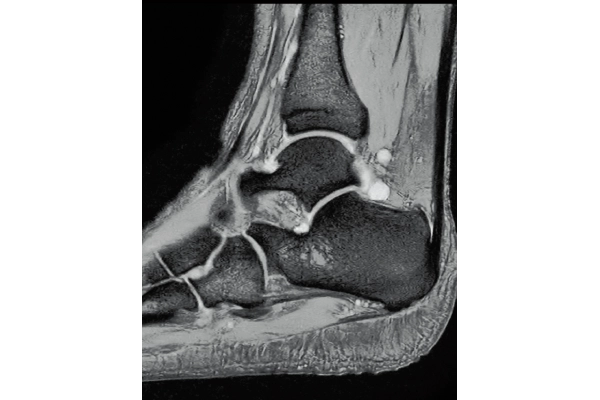

3DisoFSE T2WI

0.75×0.75×1.1(0.55)mm

MPR COR

3D Balanced SARGE

with Phase Cycling,

0.93×0.70×1.0(0.5)mm, 1:44